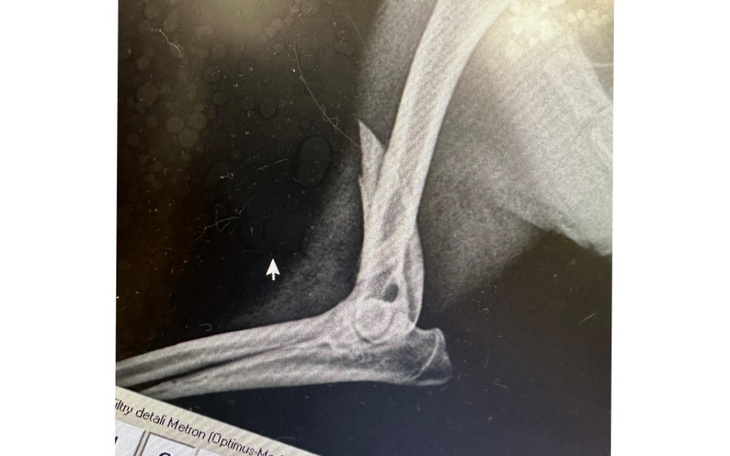

Od razu trafił do lecznicy gdzie wykonano zdjęcia RTG i dokładnie go przebadano. Psiak doznał złamania przedniej, prawej łapy z przemieszczeniem, ma duża otwartą ranę na tylnej łapie oraz otarcia na pyszku. Na szczęście nie ma obrażeń wewnętrznych ani krwotoku.

Przednia łapa musi być jak najszybciej złożona przez chirurga-ortopedę na specjalną blachę i ustabilizowana śrubami. Każdy dzień zwłoki spowoduje że złamanie będzie się przemieszczać, a psiak będzie odczuwać co raz większy ból.